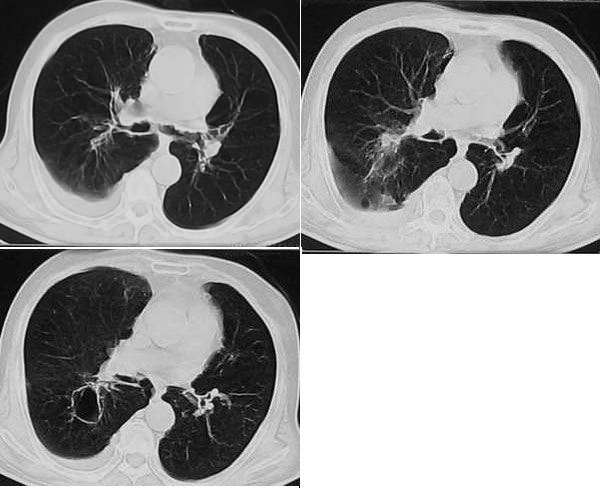

CT03371:胸部,有结果。

患者男性,80岁,长期咳嗽加重半月。

考虑恶性的东西把!

结核

首先考虑炎症,建议抗炎后复查.

考虑炎症

考虑结核